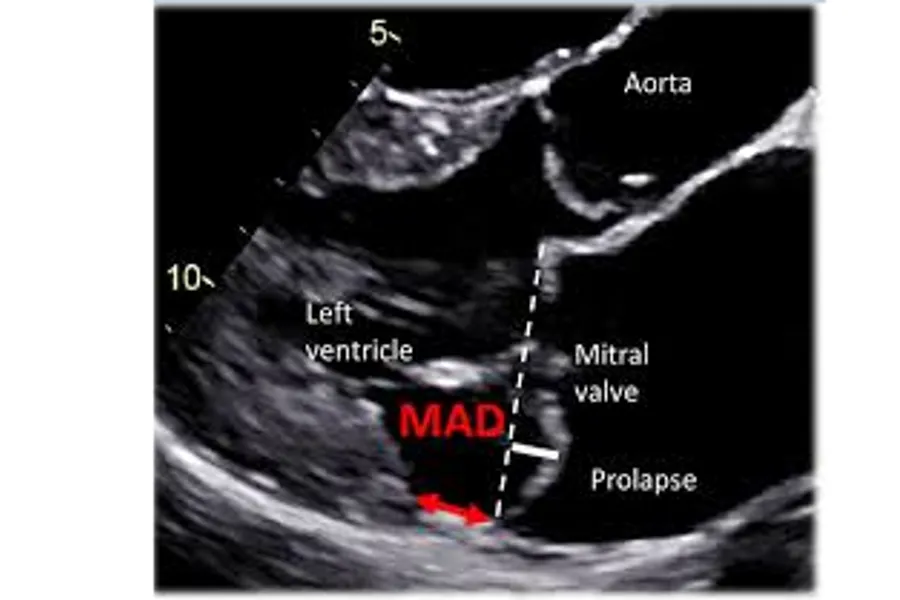

Mitral valve prolapse (MVP) is a relatively frequent valve disorder, affecting 2-4% of the general population. In most cases, the prognosis for individuals with this condition is good. However, a subset of patients with MVP are at risk of sudden cardiac death. The specific mechanisms underlying the development of arrhythmias in these individuals remain largely unknown. Mitral annular disjunction (MAD) is one of the arrhythmogenic risk factors. The genetic background of both MVP and MAD is still largely unknown and efficient therapeutic strategies are missing.

Figure: Lars Dejgaard and Kristina Haugaa, Hjerteforum 2019.

The objectives of ProCardio’s research are to uncover the etiology and mechanisms of arrhythmias in patients with MVP, including using simulation models, in order to identify potential therapeutic targets, as well as developing automatic MVP/MAD detection software.